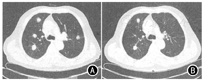

2018年8月10日到我科就诊。行CT引导下肺穿刺活检,病理诊断为(右肺)腺样囊性癌,符合转移。9月22日开始口服安罗替尼靶向治疗,1周后患者出现局部瘙痒、鼻出血症状,2周后患者出现乏力、咽痛症状,对症治疗后可耐受。10月22日行胸部CT检查,示双肺多发转移瘤,较前部分结节缩小(图1)。疗效评估为疾病稳定,遂继续口服安罗替尼。10月25日患者出现意识不清。实验室检查示,钠120.00 mmol/L,氯86.00 mmol/L,钙2.07 mmol,其他化验项目未见异常。颅脑CT检查未见异常。考虑为低钠血症所致昏迷,与口服安罗替尼有关,行补钠等对症治疗后病情好转。之后,在口服安罗替尼的同时,予以自制盐胶囊口服补钠,定期监测血钠,患者未再出现低钠血症及意识不清。至末次随访时(2019年10月21),患者已口服安罗替尼13个月,期间每2个月复查胸部CT评估疗效,病灶持续稳定。